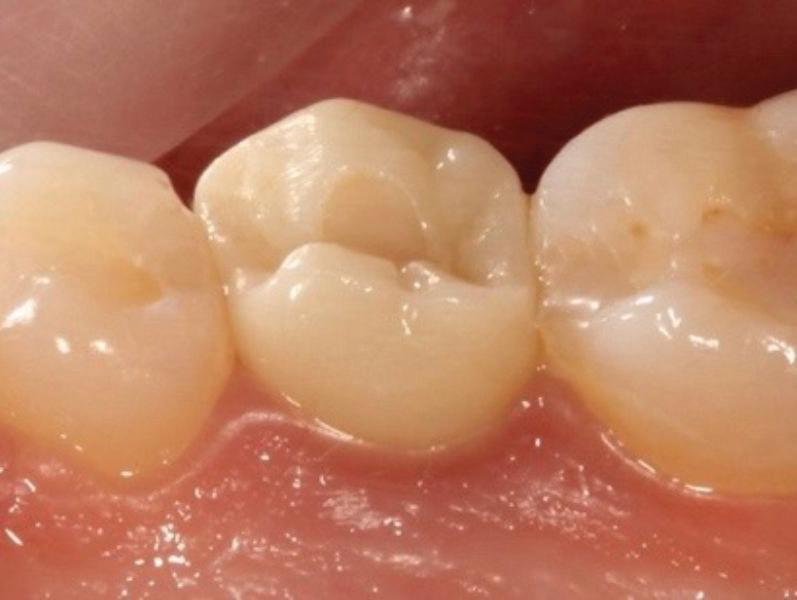

Estelite Asteria (Tokuyama)One of my favourite composite resin materials is Asteria which is a light-cured radiopaque composite for universal use. It considerably simplifies multilayer techniques yet delivers outstanding aesthetics with excellent polishability. Unlike mul tilayer techniques used with conventional composites, Asteria uses only 2 layers for optimal results without compromising aesthetics. The microstructure of the material produces a light diffusion that helps blend in with the natural tooth structure. The chameleon like nature of the material allows a blending of the materials to natural tooth structure and it allows excellent polishability which retains its lustre over time.

“Unlike multilayer techniques used with conventional composites, Asteria uses only 2 layers for optimal results without compromising aesthetics.

The microstructure of the material produces a light diffusion that helps blend in with the natural tooth structure...”